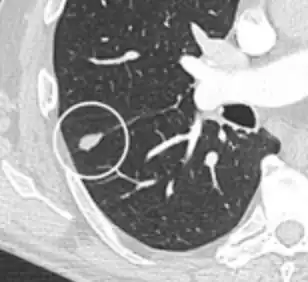

- A lung nodule abutting a pulmonary cyst is a rare finding, yet indicating cancer.[9]

- Bubble-like lucencies in the nodule indicate cancer:[9]